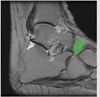

Sensory loss posterolateral aspect of leg and lateral aspect of foot